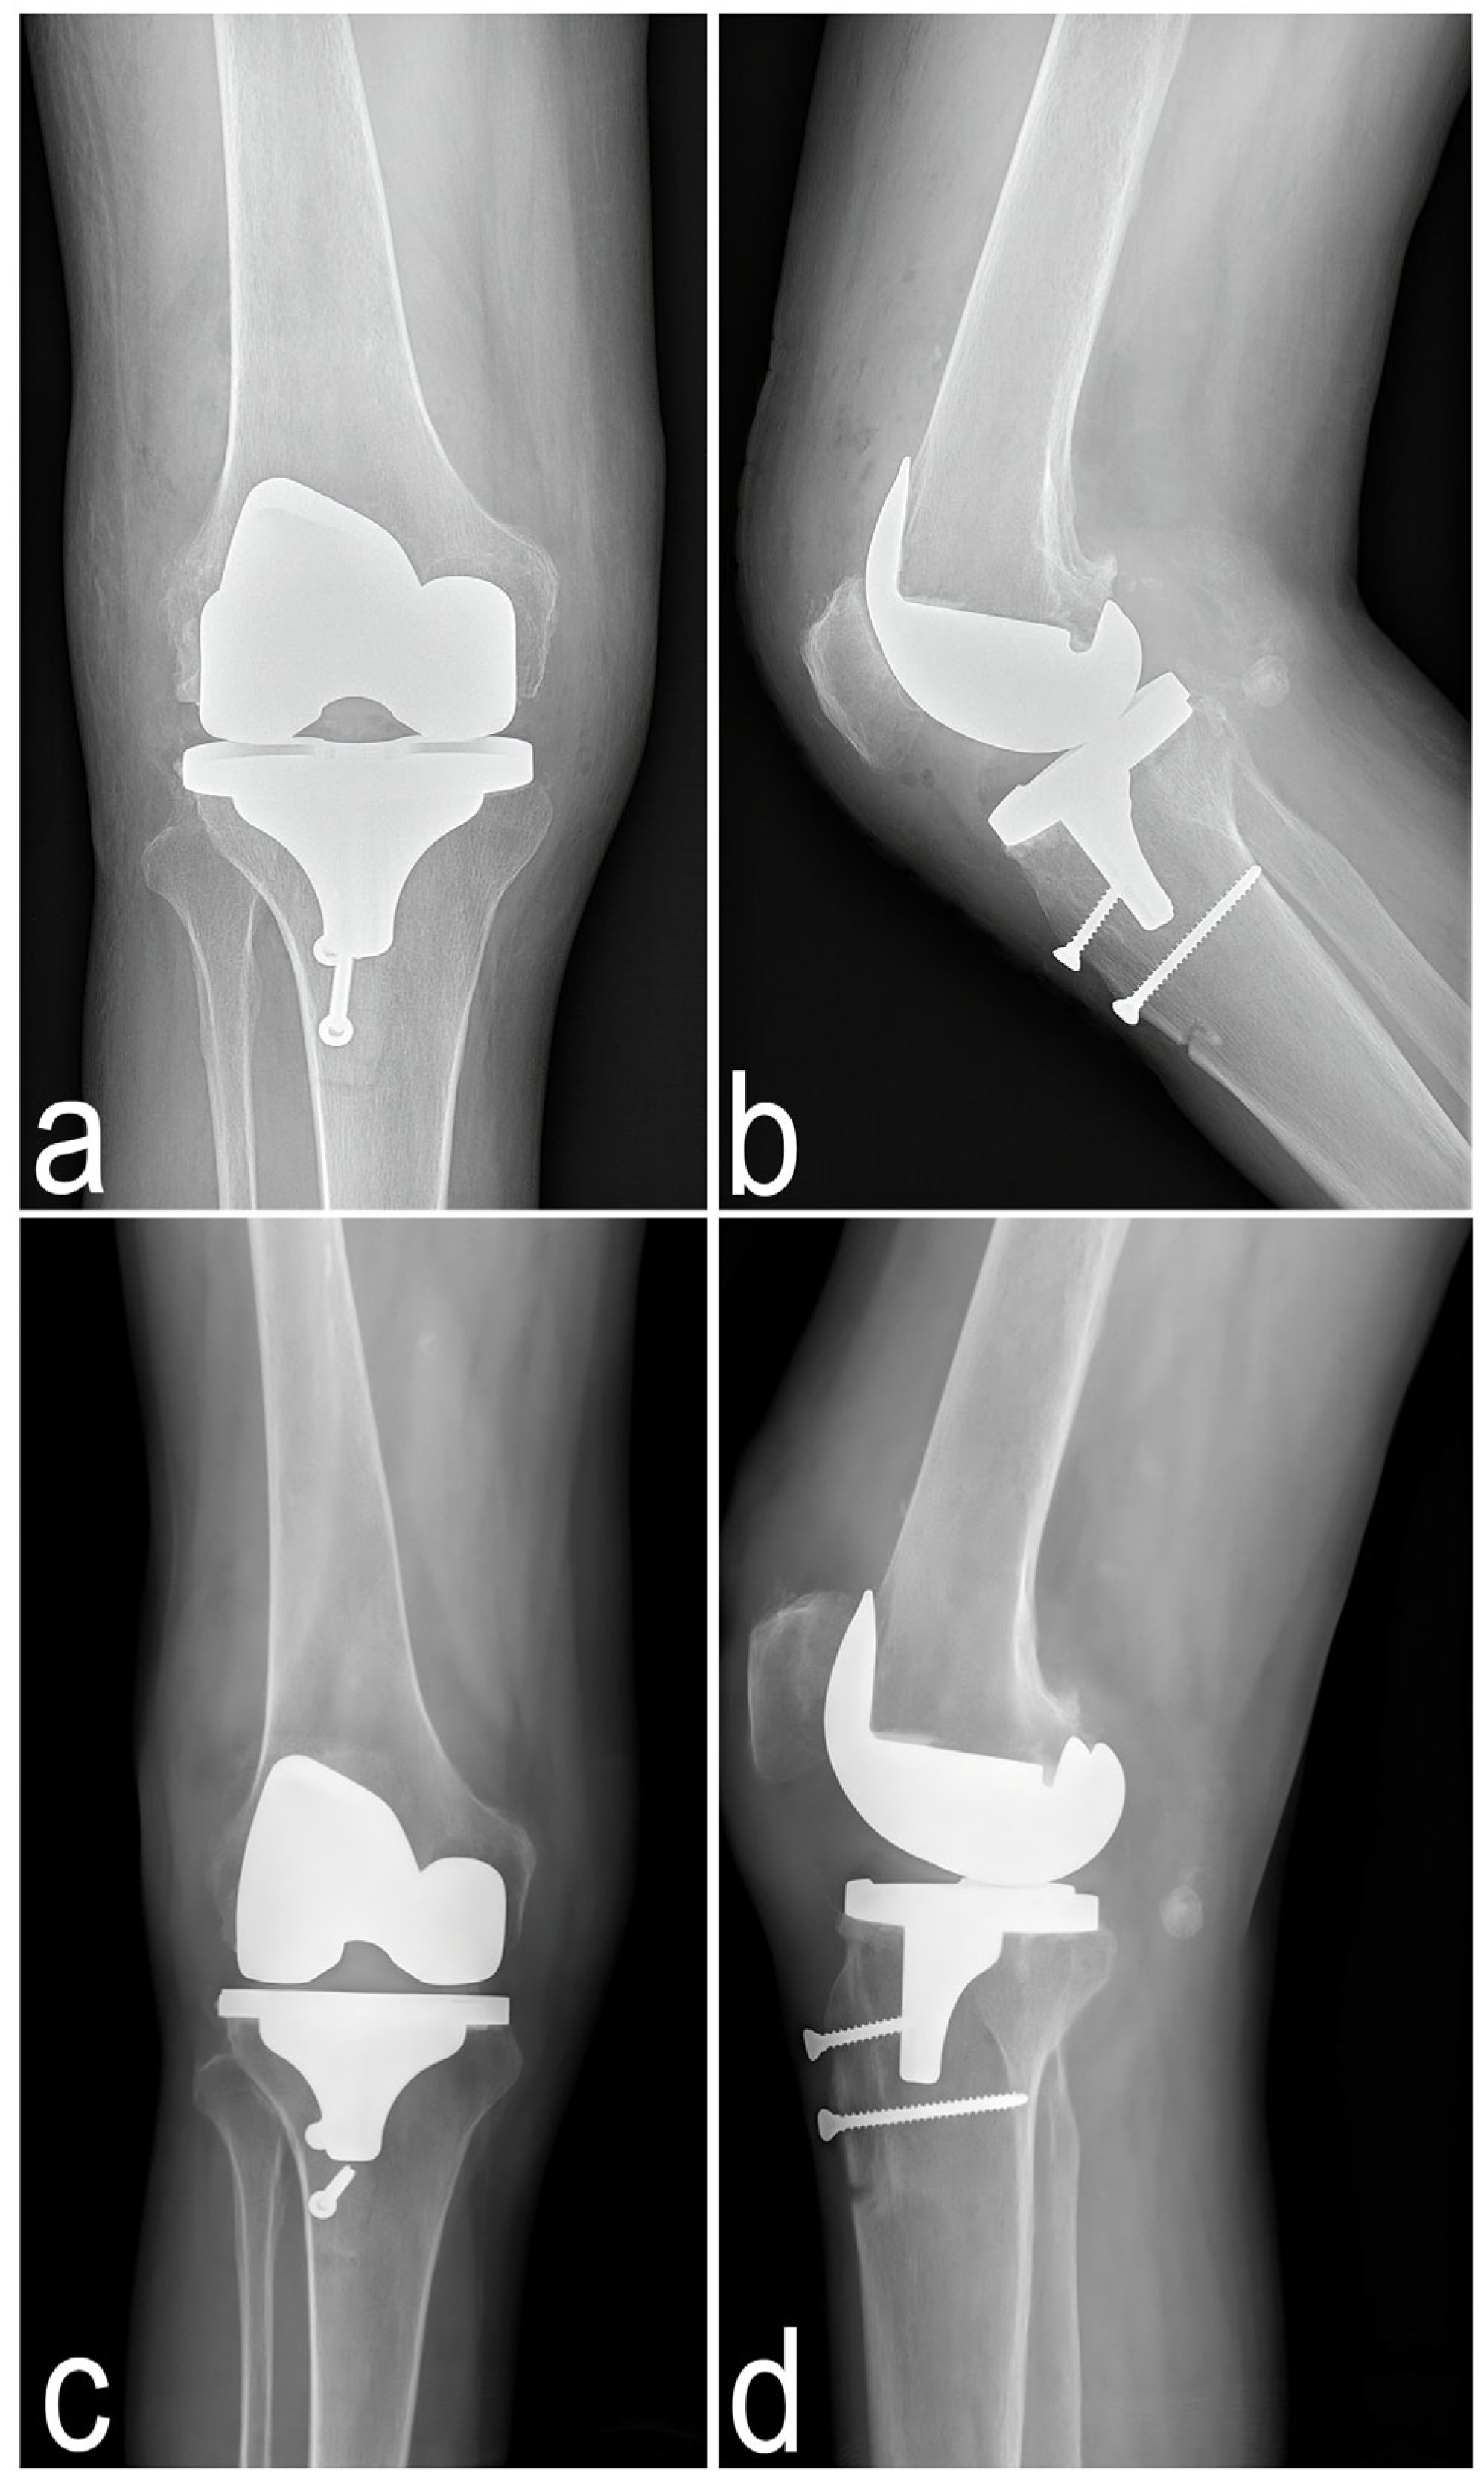

2.2. Surgical Treatment

2.4.2. Imaging Examination

2.5. Innovative Applications of the MyotonPRO Examination for the Assessment of Muscle Condition Before and After Knee Arthroplasty in a Patient with Alkaptonuria